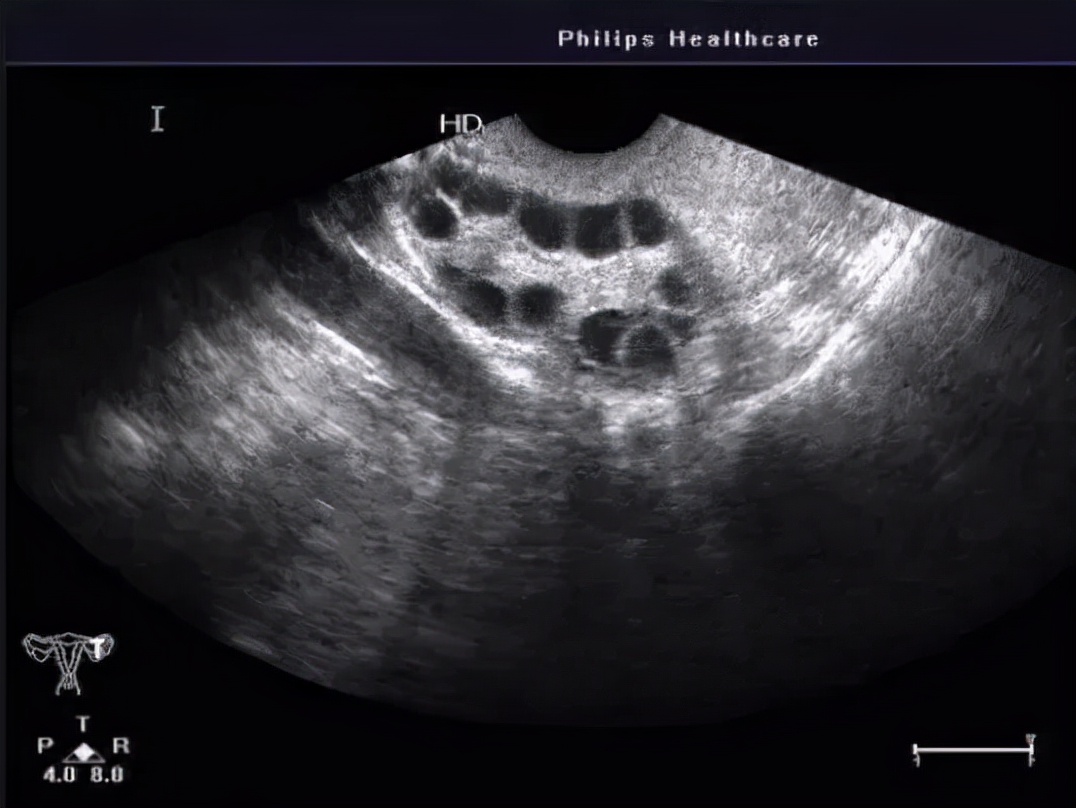

04 多囊卵巢综合征

单侧或双侧卵巢呈现多囊性改变,即沿着卵巢外周有10个左右均匀的卵泡,俗称“项链征”,详见“ 月经不正常-多囊卵巢综合征 ”。这类囊肿还是很好鉴别的,需要结合月经情况、雄激素水平综合诊断及药物治疗,无需手术。